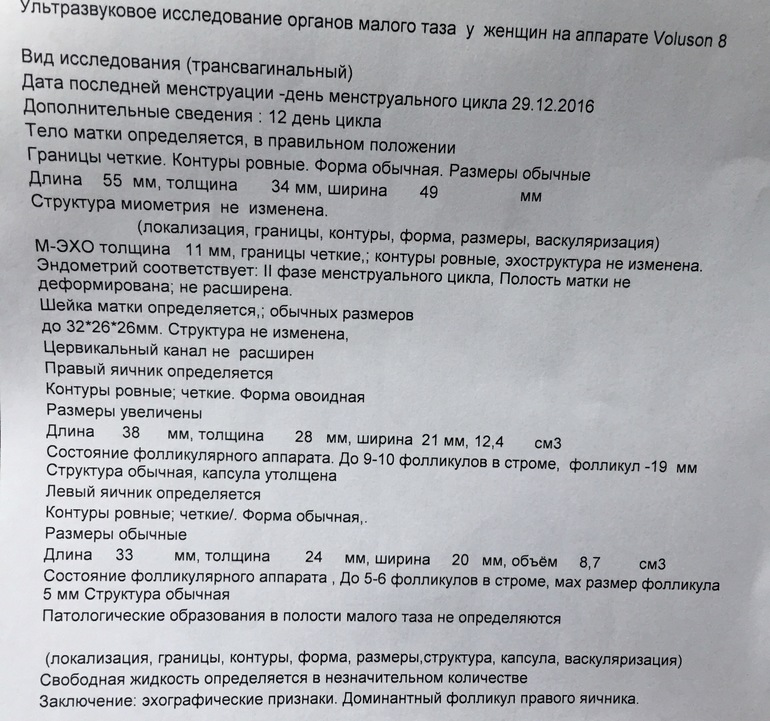

УЗИ после положительного теста на О. клеар блю

С утра сделала УЗИ. Ниже результаты. По О. специалисте сказалась что есть косвенные признаки, что О. была. Но в првом яичнике есть доминантный фолликул. 13 иду на повторное УЗИ, посмотреть была ли О., так как мне летом ставили СПКЯ,хотя сейчас врач сказала, что все нормально. Может кто разбирается в УЗИ?Она мне толком ничего и не объяснила.

Овуляция уже была - эндометрий соответствует второй фазе цикла и как подтверждение обули - наличие свободной жидкости, узистка, простите, должна это знать, не зачем идти на повторное УЗИ, а в правом яичнике - подвергнется ретроградному развитию, должен)

У вас все хорошо. Овуляция еще не наступила. Есть доминантный фоликул в пя

Он еще не лопнул. Когда лопнет должна выйти яйцеклетка из яичника и тогда возможно зачатие

Вот врач мне и сказала,что либо лопнет,либо киста и нужно сделать УЗИ 13.01.17

О уже была т.к есть свободная жидкость. Эндометрий хороший. Не переживайте.

я тоже считаю что О еще не было, т.к ЖТ нет,вот будет на днях, а жидкость в неб количествах это вариант нормы /физиологическая норма.У меня тоже до О была жидкость в неб кол-ве, потом ДФ лопнул и была и жидкость и ЖТ. ДФ в среднем на 2 мм в день растет.. так что ждите О)))